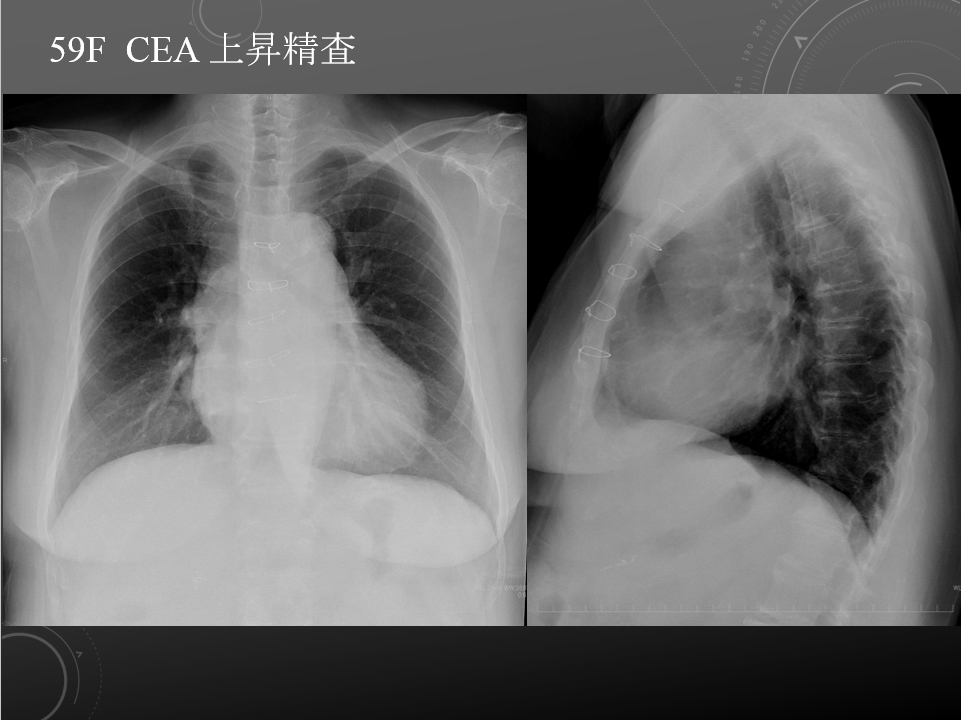

59F 甲状腺癌、上行結腸癌、S 状結腸癌術後、CEA上昇

68F CEA 高値精査。消化器内科依頼。既往に脳梗塞、心筋梗塞、胃ポリープあり。

右肺下葉腺癌。

右肺下葉の縦隔側には最大径31mm大の不整形な腫瘤性病変を認めます。表面には部分的にspicula所見が見られ、胸膜に広汎に隣接するように存在しています。内部は辺縁を中心に淡い造影効果を呈しています。原発性肺癌病巣が疑われます。肺門部にはリンパ節腫大像が見られますが、縦隔領域に明らかに有意なリンパ節腫大は指摘出来ません。

左肺下葉に末梢側には淡い濃度上昇所見が見られ、GGO病変が疑われます。この他、肺野に明らかな腫瘤性病変は指摘できません。

肝内に占拠性病変は認められません。

明らかな副腎腫瘤は指摘できません。

両腎には嚢胞と考える低吸収像を認めます。

胸腹水貯留は見られません。

腹壁瘢痕ヘルニア所見を認めますが、明らかな腸管の逸脱は見られません。

・Lung cancer s/o

SUVmaxは10.2

右肺下葉内側の腫瘤に一致して異常集積を認める。